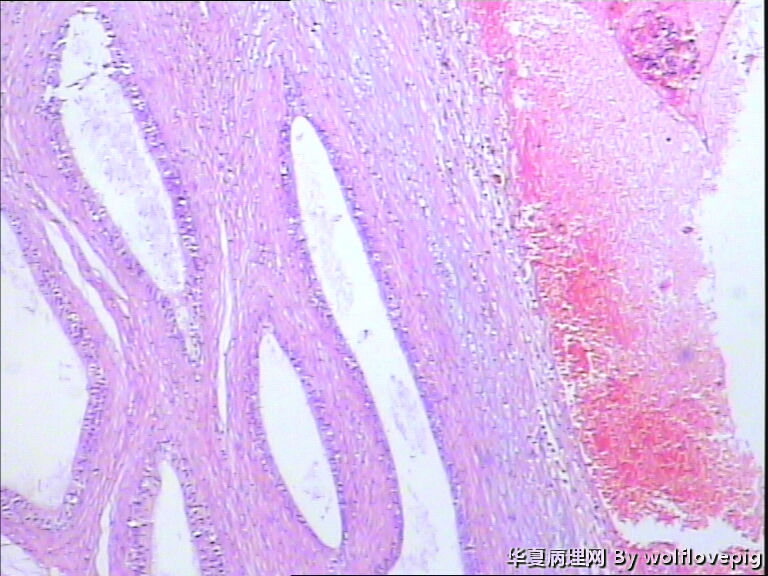

62y,双侧附睾。

临床怀疑结核,以附睾结节切的,取材时未发现明显结节。

送检附睾管囊性扩张,管腔结构较完整,多数管腔内见精子积聚,少数管腔内有出血。

取材切片附睾管扩张,精子淤积,部分区域出血

未见肉芽肿结构,也未见其它异常。